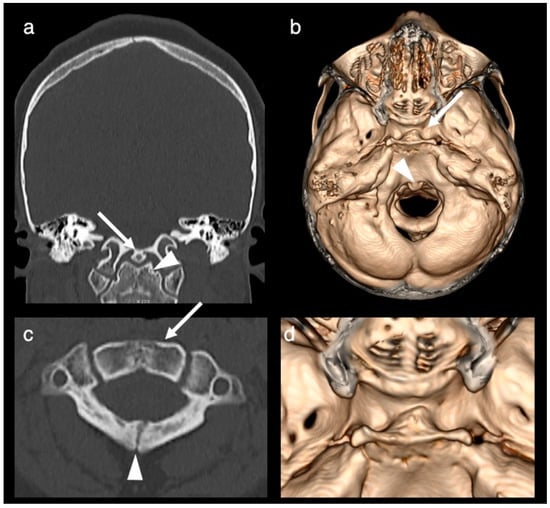

2. Case Report